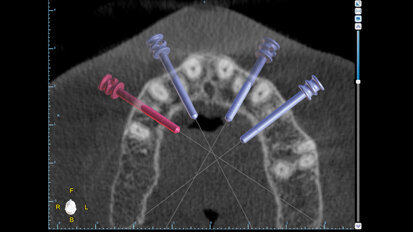

Fixní rekonstrukce celého oblouku nesená implantáty: Využití „full-template guidance technique"“

Fixní rekonstrukce celého oblouku nesené implantáty vyžadují správnou diagnostiku a plánování léčby. Jen tak je možno zhodnotit stávající ...